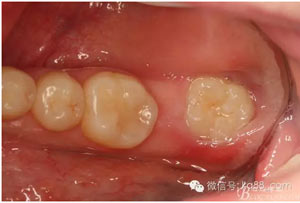

圖2.術(shù)前口內(nèi)照:37未萌出。38牙冠近中傾斜?;颊哒衬ど珴烧#瑹o瘺管、無滲出。

2.jpg